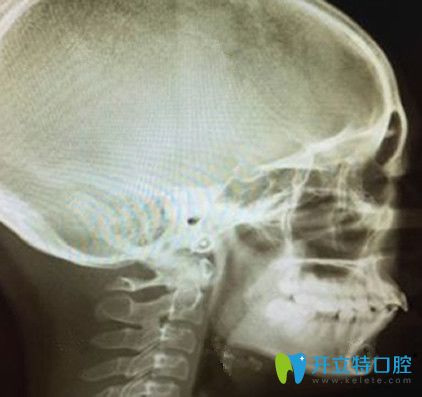

牙齒矯正術(shù)前拍片側(cè)面牙齒照片:

牙齒矯正術(shù)前拍片側(cè)面牙齒照片

首先,正畸的開始需要拍兩張x光片,確定牙齒問題是齒性還是骨性,或者是有沒有什么其他的肉眼無法解決的問題。

從這張側(cè)面的X光片看我不僅突嘴,而且似乎還少了一顆牙,嗚嗚嗚……真心想哭。